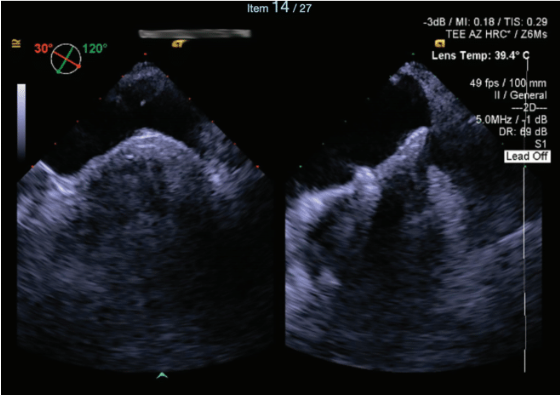

After completing the ablation and confirming non-inducibility, the catheters and Agilis sheath were carefully removed from the LA. Postprocedural imaging of the ASD showed no measurable defects. The venipuncture site (8 French) was closed using the MynxGrip device (Cordis), and anticoagulation was reversed. The patient recovered for 2 hours while supine and was subsequently discharged home approximately 2.5 to 3 hours post-procedure from the ASC.

TEE can be a superior tool in guiding transseptal puncture, particularly in complex AF cases, where anatomical challenges such as a prior ASD or patent foramen ovale (PFO) closure device are present. TEE provides real-time, high-resolution imaging that enhances the precision of catheter placement during transseptal puncture, reducing the risk of complications associated with inadvertent puncture of adjacent structures. In patients with prior large ASD or PFO devices, where the anatomy of the interatrial septum may be significantly altered, the ability of TEE to clearly delineate the septum and device margins is invaluable, ensuring that the puncture is performed safely and accurately. This utility makes intraprocedural TEE an essential modality in the management of such high-risk cases, optimizing outcomes and minimizing procedural risks. Although we frequently utilize ICE during AF ablations, our operators prefer the utility of TEE when encountering challenging transseptal punctures such as this case. The limitations of obtaining consistent access to intraprocedural TEE given the scarcity of cardiac anesthesia coverage is an unfortunate reality; however, we specifically request such assistance and plan for this coverage when facing complex transseptal puncture cases.